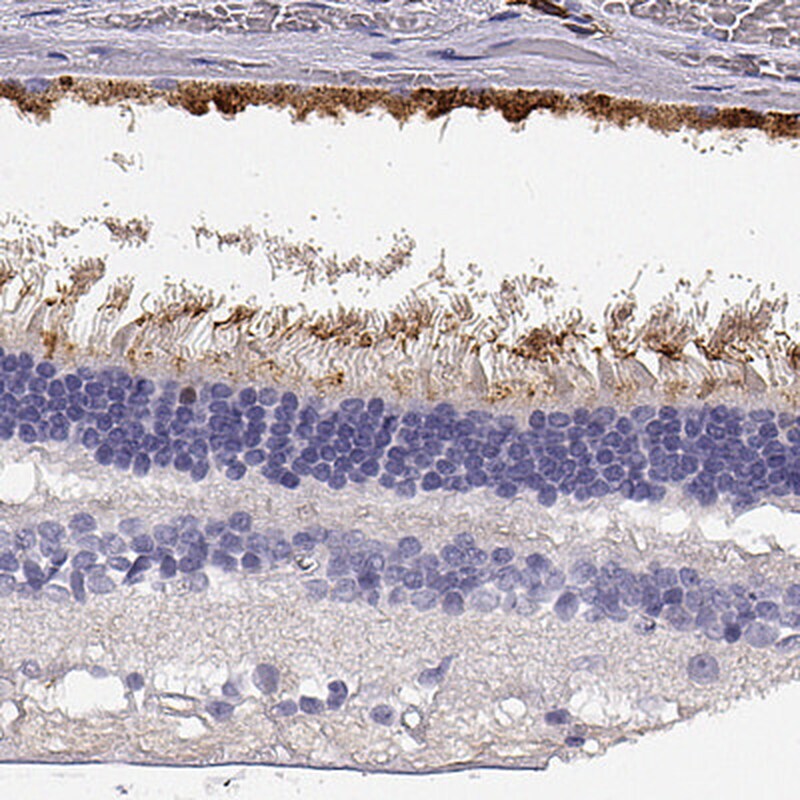

- Submitted by

- Invitrogen Antibodies (provider)

- Main image

- Experimental details

- Immunohistochemical staining of CDHR1 in retina using a CDHR1 Polyclonal Antibody (Product # PA5-57832) shows strong cytoplasmic and membranous positivity in photoreceptors.